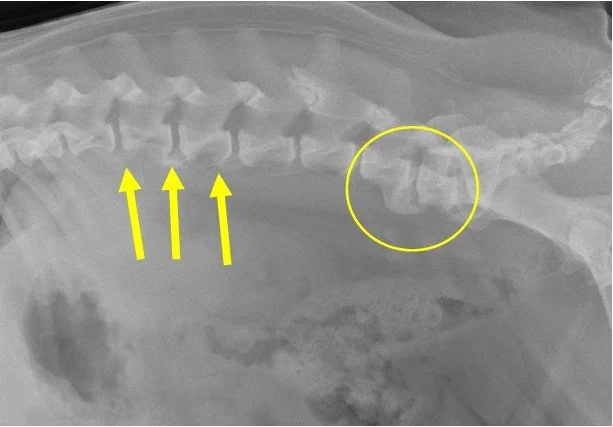

He has no real use of his back legs. They were froze/locked in a rigid position, so he used them to steady his back end, but he wasn’t able to actually move them in any useful way. X-rays of his spine showed a major deformity that he was likely born with. The shelter didn’t have the resources to care for this kind of disability. They called us before making the decision to euthanize him.

Bernie came to us from one of our shelter partners after being hit by a car, which rendered him a paraplegic (no use of his back legs). Shelter staff thought maybe he had a broken pelvis, but we had a hunch that it was an injured spine. We took him straight to our vet for x-rays. Good news was it wasn’t a fractured pelvis, nor a fractured spine. Instead, it was two compressed spinal discs. More good news was that although he couldn’t use his back legs, he appeared to be continent (able to pee and poop on his own). We started him on a steroid (prednisone) to reduce the inflammation and put him on strict cage rest. Lab work also indicated that there was trauma to his liver, so we started him on liver supplements. After a few weeks, he regained the use of his back legs and his liver returned to normal. We are in the process of seeing if acupuncture may help his continued recovery. Unfortunately, however, due to this spinal trauma he is at risk of re-injuring the spine. Potential adopters will need to insure that he doesn’t jump off furniture nor over do it with too rigorous exercise.